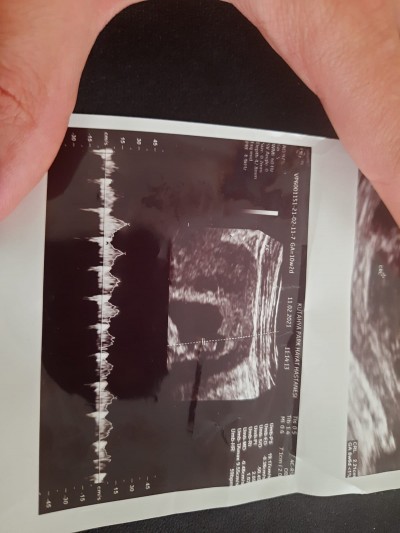

Çok erken biliyorum ama merak ediyorum tahmin eden yazabilir mi?

Gebelik haftası 11+4